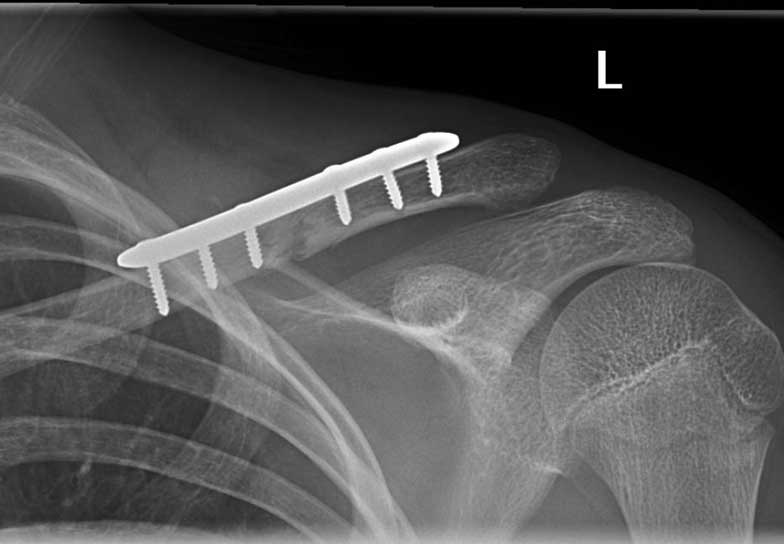

Generally all displaced fractures of the distal clavicle require surgery to increase the incidence of union. In my practice, the operation is performed by realigning the bones back to their original position using a plate and screws on top of the bone. The advantage of fixing them with a plate and screws generally means that you can start to move the arm a lot quicker and to also decrease the incidence of non-union.

How is the Operation Done?

The operation is performed with the patient under a general anaesthetic, in other words, completely asleep, and a small 3-4 cm incision is made under the collarbone, at the end of the shoulder. The fractured bone ends are exposed and put back into position using a plate and screws as shown below.

Click an image to enlarge

This fixation also needs reinforcement using special sutures around the plate and around the bone next to the clavicle called the coracoid process. The sutures are used to decrease the deforming forces from your shoulder muscles. In the majority of cases, in my hands, the operation is extremely successful resulting in the bone healing and the return of near normal function. In a small number of cases, the plate needs to be removed if it irritates the patient under the skin.